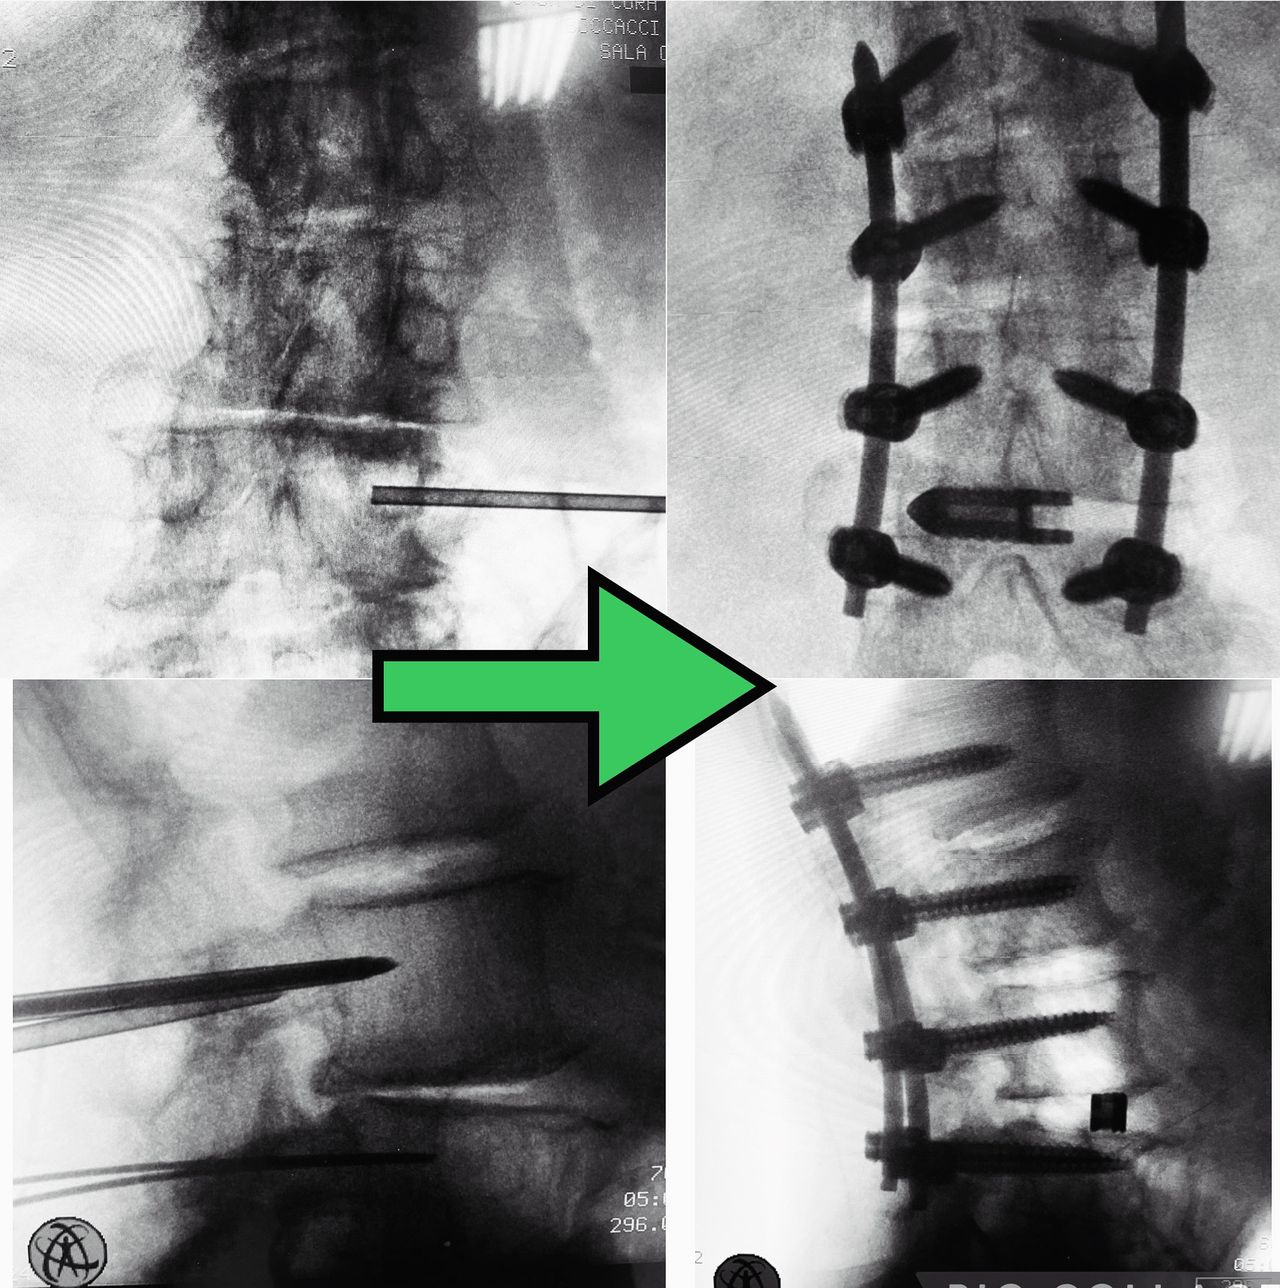

- Chirurgia Mininvasiva percutanea vertebrale - stabilizzazioni e artrodesi intersomatiche (per fratture vertebrali, spondilolistesi, instabilità vertebrali, discopatie)

- RX scopia intraoperatoria